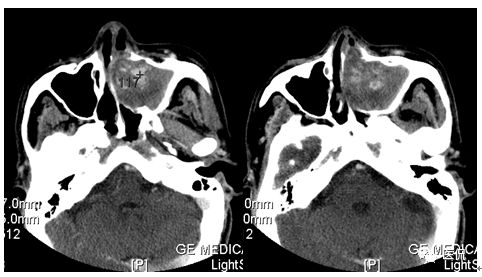

增强静脉期

CT平扫及增强示:左侧上颌窦及鼻腔可见软组织密度影,呈膨胀性生长,周围骨质压迫性吸收破坏,累及左眶,病灶密度不均匀,周边区可见点状钙化,增动脉期轻度强化,局部见小灶性稍高密度区,静脉期病灶内见不均匀明显强化,CT值最高达117HU,延迟期强化范围有所增大。

本例病灶较大,周围骨质可见吸收破坏,并累及眼眶,病灶内少量钙化,增强扫描具有一定特征性,表现为动脉期轻度强化,局部见小灶性稍高密度区,静脉期病灶局部呈明显强化,CT值最高达117HU,延迟期强化范围有所增大,呈延迟渐进性强化的特点,推测为病灶内出血所致。